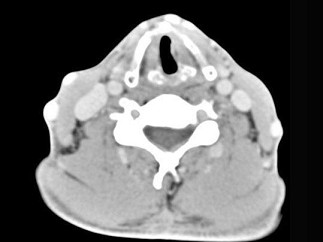

男,50岁,自觉咽喉部不适一个多月,间断刺激性咳嗽,CT扫描如图所示,正确的描述或诊断是()

A.左侧声带内侧壁见结节状影向腔内突出,以宽基底与声带相连

B.增强扫描结节强化不明显,密度均匀,周围结构未见受侵

C.左侧声带息肉

D.左侧声带乳头状瘤

E.喉癌

[多选题]男,50岁,自觉咽喉部不适一个多月,间断刺激性咳嗽,CT扫描如图所示,正确的描述或诊断是()A.左侧声带内侧壁见结节状影向腔内突出,以宽基底与声带相连

[多选题] 男,50岁,自觉咽喉部不适一个多月,间断刺激性咳嗽,CT扫描如图所示,正确的描述或诊断是()A . 左侧声带内侧壁见结节状影向腔内突出,以宽基底与声带相连B . 增强扫描结节强化不明显,密度均匀,周围结构未见受侵C . 左侧声带息肉D . 左侧声带乳头状瘤E . 喉癌